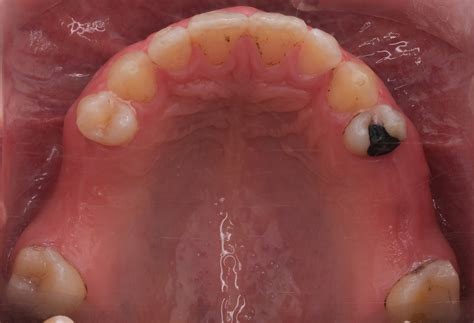

Orthodontic Correction of Midline Diastema in Aggressive Periodontitis

Orthodontic Correction of Midline Diastema in Aggressive Periodontitis ...